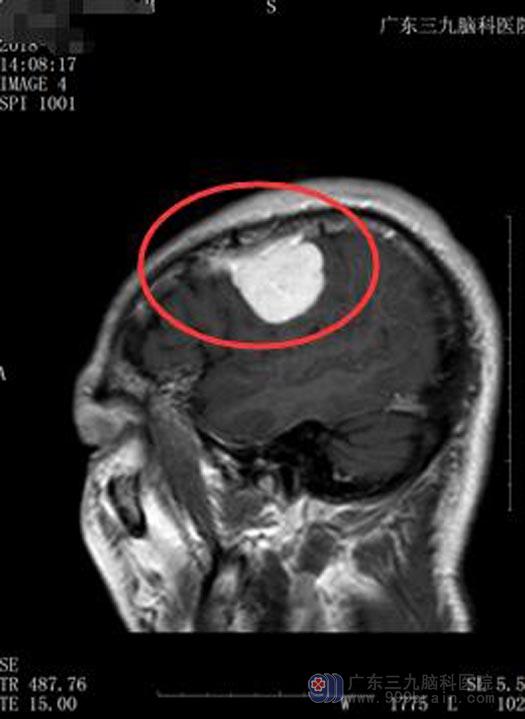

入院后MR检查确诊为左侧额部脑膜瘤。鲁明副院长告诉他们,脑膜瘤属于良性肿瘤,生长慢,病程长,呈膨胀性生长;因肿瘤生长缓慢,所以肿瘤往往长得很大了,临床症状还不严重,多数是偶然发现。随着显微手术技术的发展,脑膜瘤的手术效果不断提高,手术切除脑膜瘤是最有效的治疗手段,大多数病人能得以治愈。

家属同意行“左侧额部脑膜瘤切除术”。术中见肿瘤明显侵犯脑膜,边界较轻,血供丰富,显微镜下整块全切肿瘤。术后张先生康复很快,已满意出院。

手术前